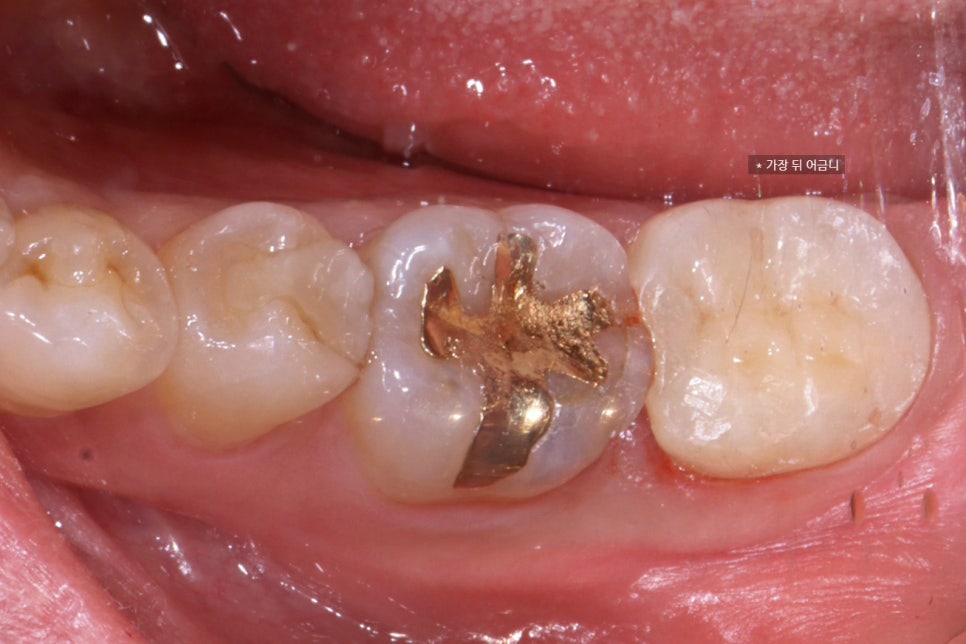

치료 완료

이렇게 잘 치료 되었습니다 :-)

1주일동안 임시합착하여 괜찮으신지 지켜보았고

최종 마무리후에 사진을 찍었어요.

사실 앞에 금인레이 한 치아에도 금이 많이 가 있고

그 앞에 인레이한 치아도

인레이와 치아 사이가 들떠있어서

상태가 썩 좋지는 않습니다.